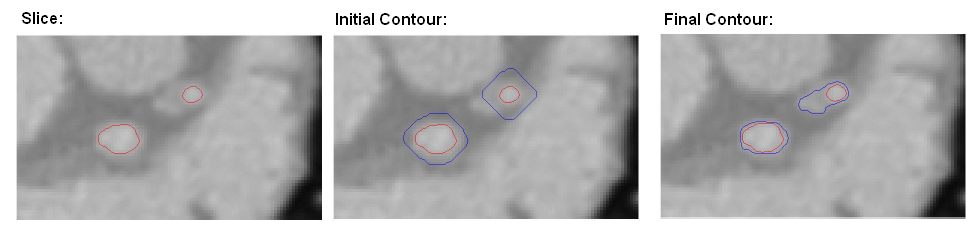

Results of local region based evolution in 2D

The results of the local region based evolution on a 2D slice of CTA volume is given below. The Red contour is the output of the vessel segmentation algorithm discussed in the previous section. The Blue contour is the result of the local region based evolution using Chan-Vese energy. The region between the Red and the Blue contour is the soft plaque and the wall of the coronary vessel.

Figure 8

Fig. 8.